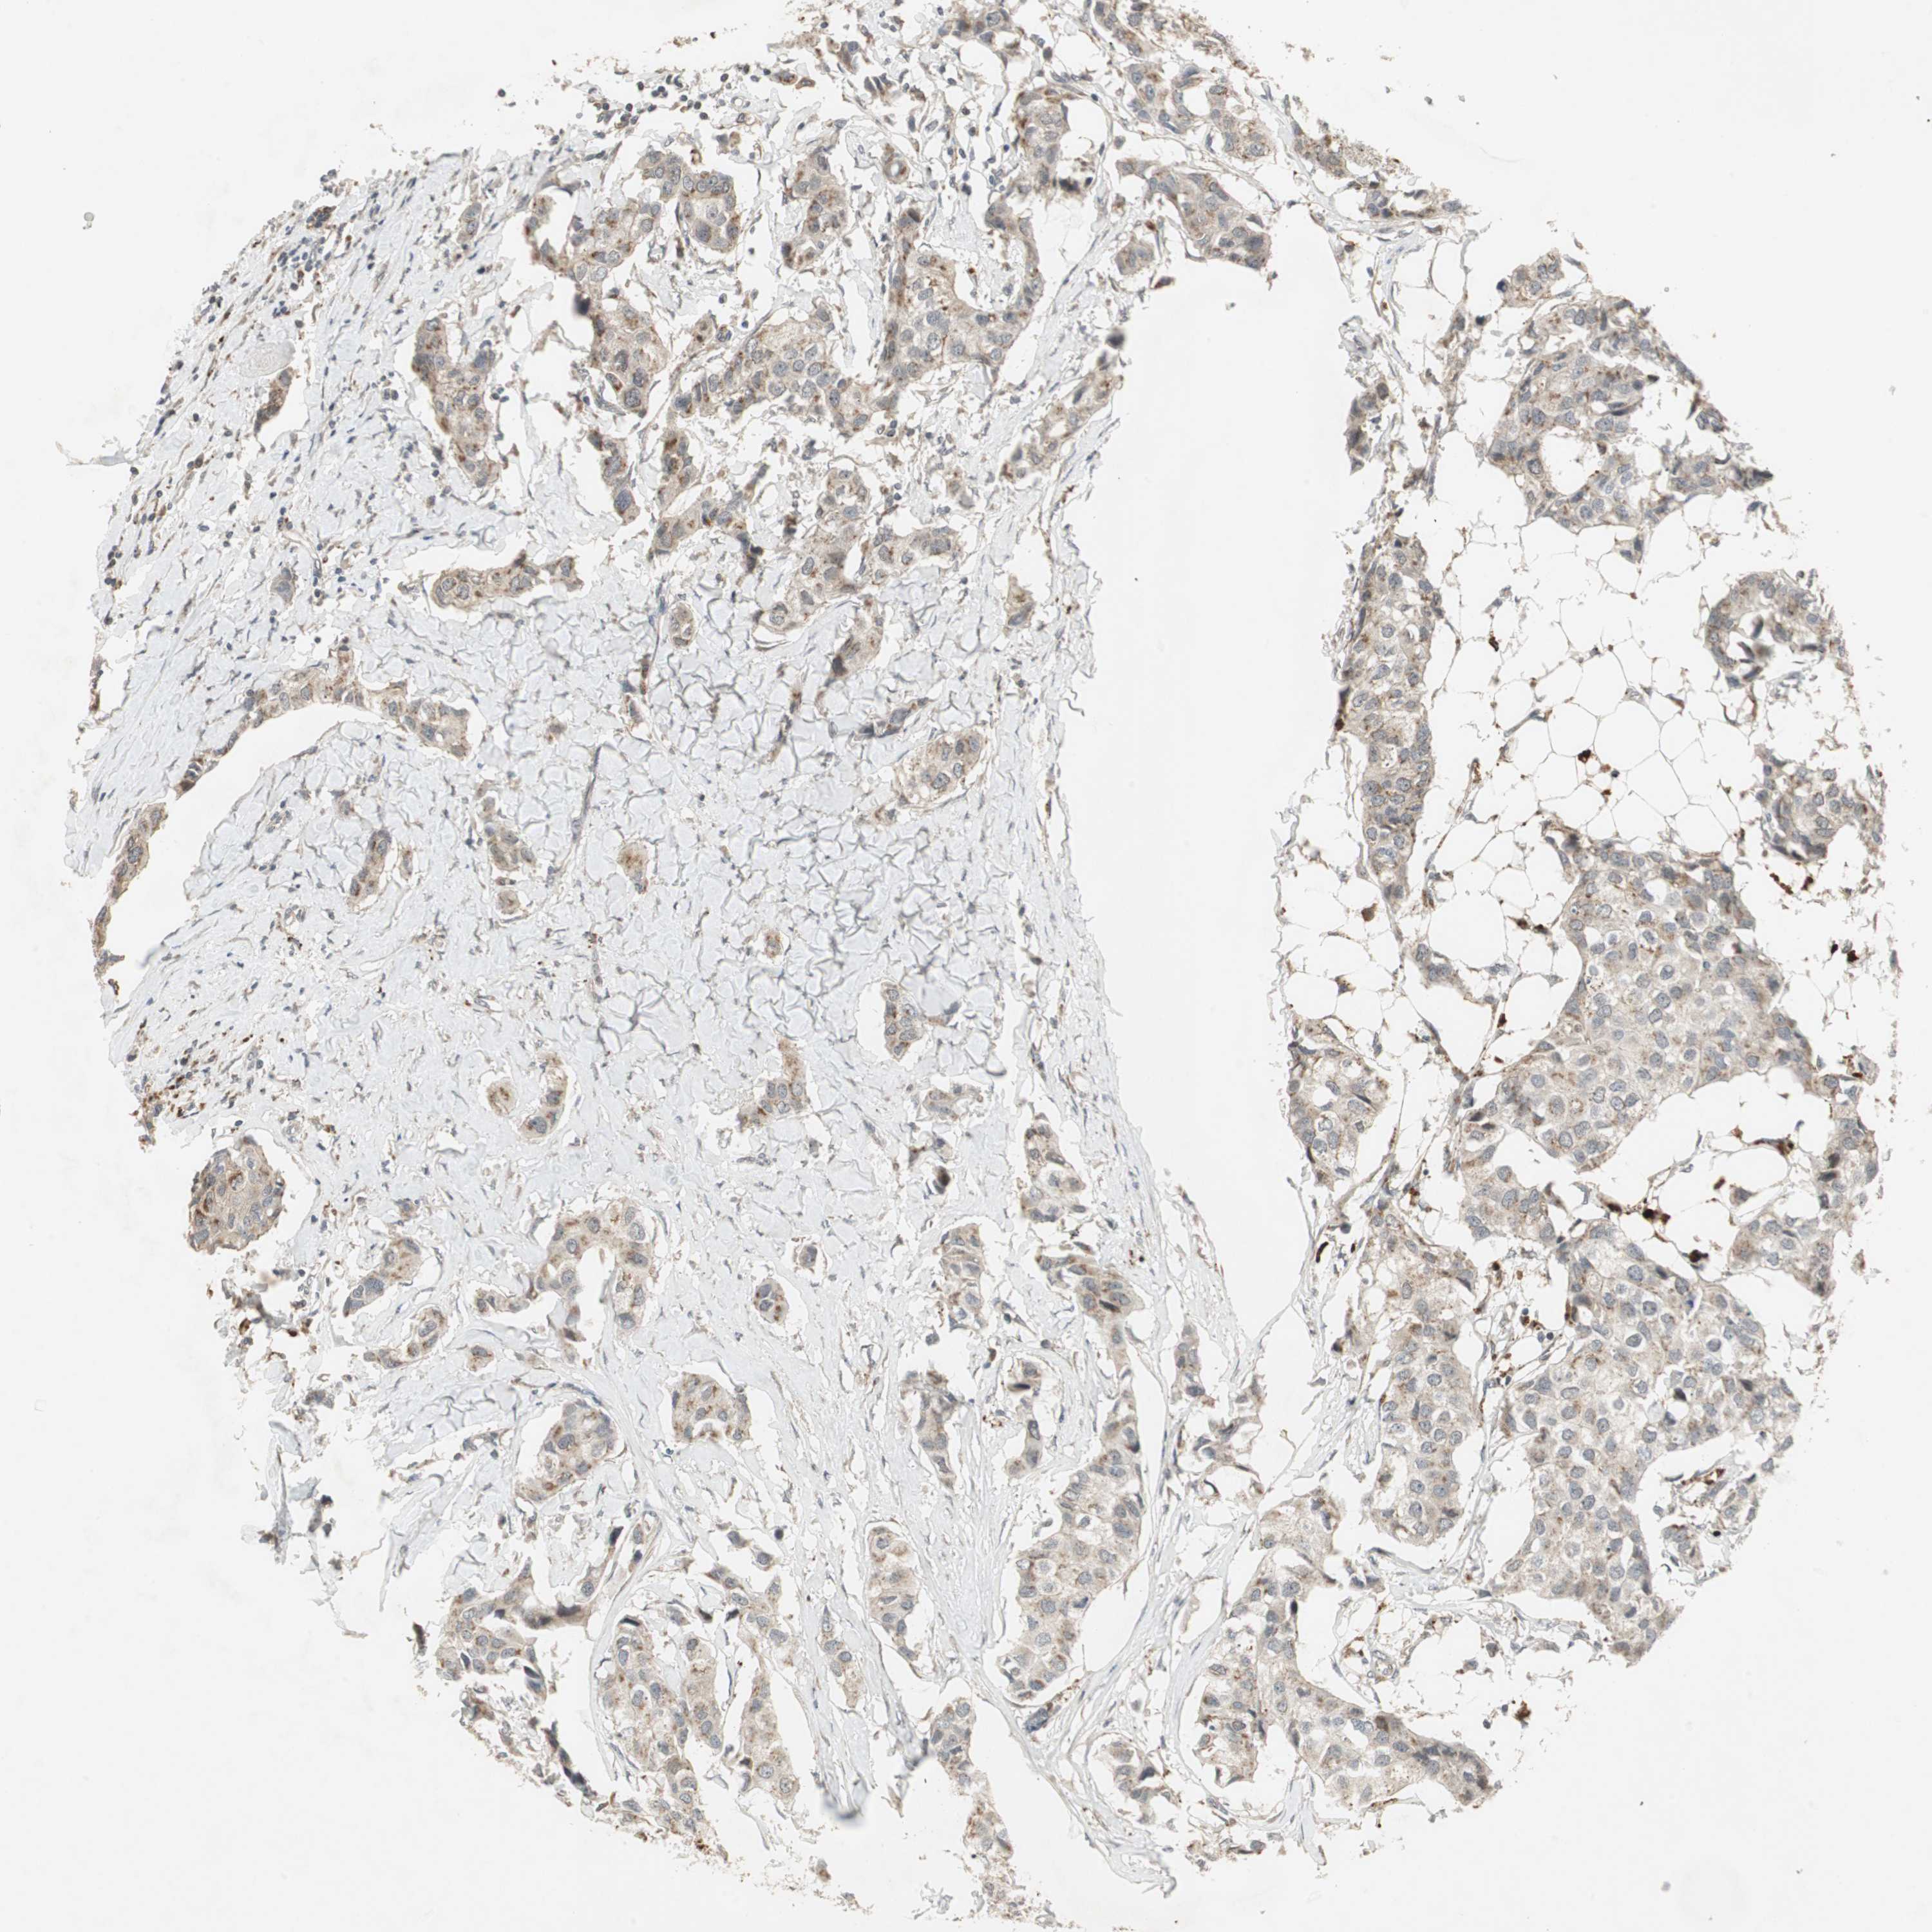

CANCER BREAST CANCER Show tissue menu

BRCA TCGA BRCA VALIDATION PROTEIN EXPRESSION

ANTIBODIES